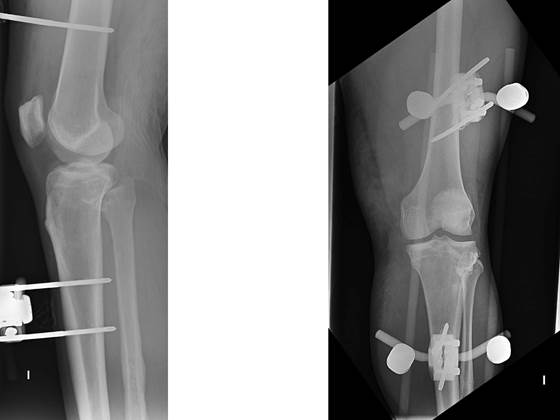

Hombre de 24 años, obeso, derivado de urgencias de AP por dolor, deformidad e impotencia funcional de la rodilla izquierda tras caída en bicicleta. No presenta heridas externas. En urgencias, tras asegurar la presencia de pulso distal y sensibilidad, procedemos a una valoración radiológica (figura 1), donde apreciamos una luxación anterior femorotibial. Bajo sedoanalgesia, reducimos la luxación y revaloramos la integridad neurovascular. Exploramos la integridad ligamentosa apreciando inestabilidad multidireccional: cajón posterior +++ y valgo +++. Inmovilizamos a 30º con férula posterior, comprobamos radiológicamente la reducción, sin apreciar fracturas, y derivamos al paciente a nuestro hospital de referencia, donde una angiotomografía computarizada (angio-TC) descarta lesiones vasculares, pero detecta una fractura de hundimiento de la cara anterior de la meseta tibial externa (figura 2), confirmada posteriormente con una resonancia magnética (RM), que además determina las lesiones musculoesqueléticas asociadas a la luxación: rotura de ligamento cruzado anterior (LCA), rotura parcial del ligamento cruzado posterior (LCP), rotura del ligamento colateral medial (LCM), rotura del tendón semimembranoso y tendones de la pata de ganso, y rotura del menisco interno. Se inmoviliza con fijador externo (figura 3) y se interviene 18 días más tarde, iniciando la rehabilitación al día siguiente, inicialmente con movilización suave, carga progresiva desde el primer mes, bicicleta sin resistencia a partir del segundo mes y piscina. Como secuela, 6 meses después de la lesión, presenta un leve bostezo en valgo que no le impide caminar. Dos años más tarde, hace vida normal, incluyendo laboral y deportiva.